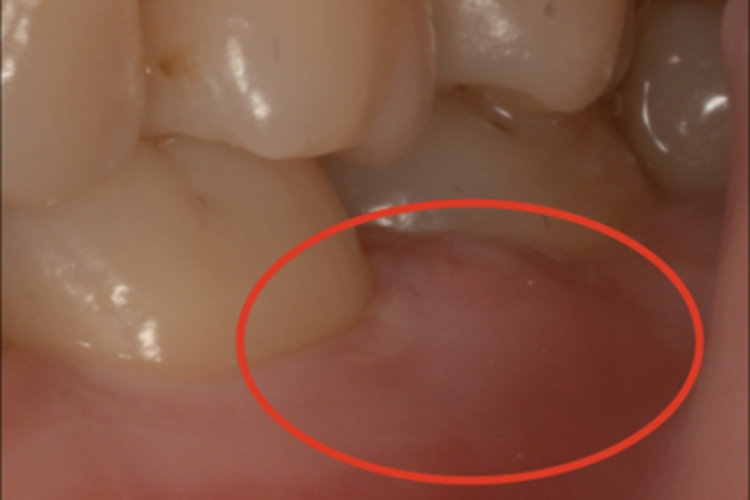

侵袭性牙周炎在活动期,牙龈有急性炎症,检查可见患者的牙龈上出现脓肿,边界模糊,高于周围正常黏膜,表面微微发红。患者可自觉疼痛。